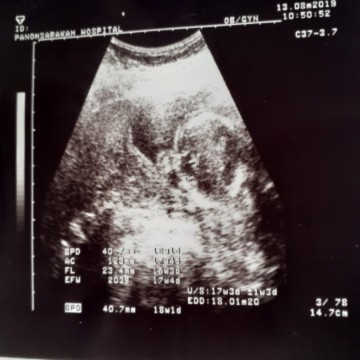

18 week 3 day